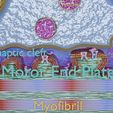

神经肌肉接头示意图

/https://fbi.cults3d.com/uploaders/27147996/illustration-file/829f118f-c1e4-417e-a8c4-14d13cca8920/sig2.jpg)